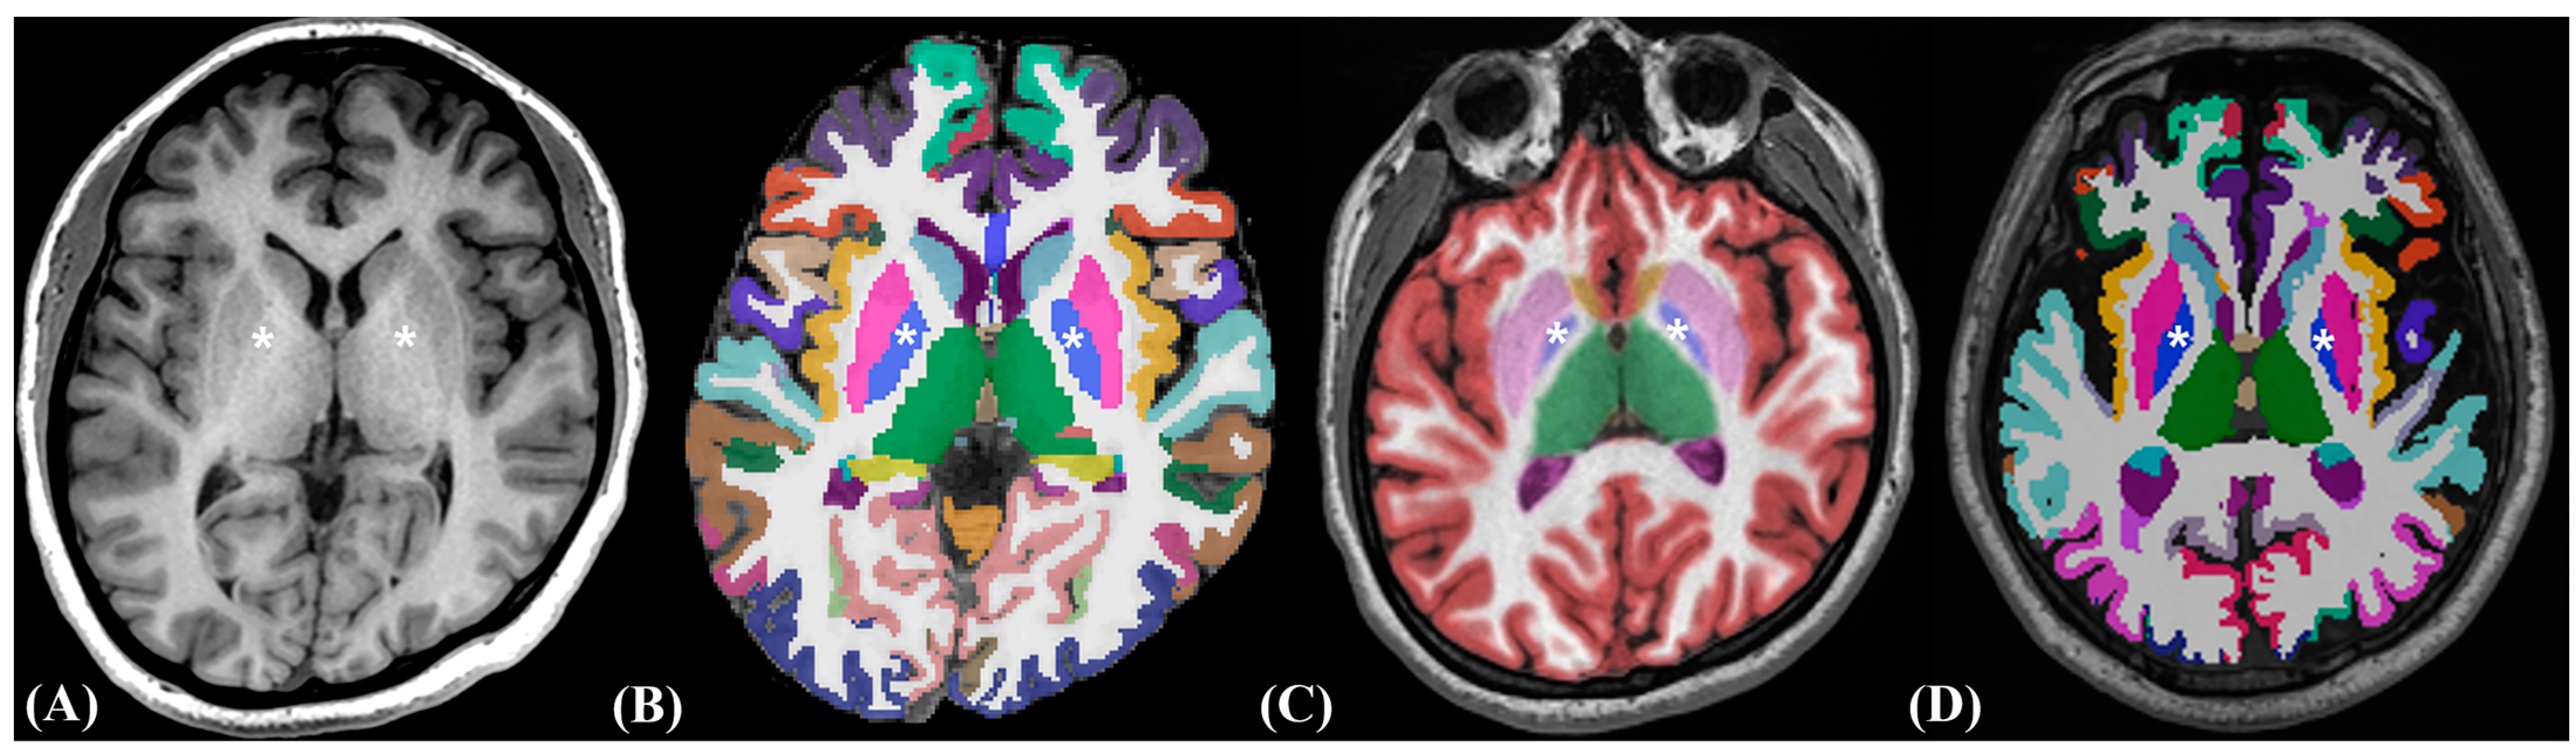

2.3. Image Post-Processing Volumetric Procedures